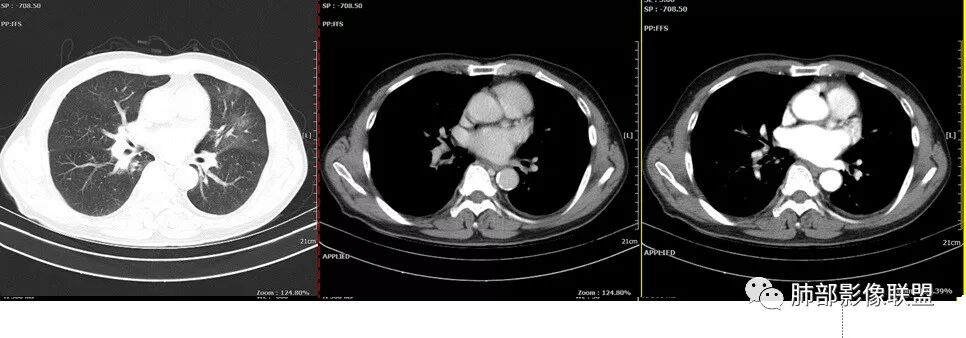

胸CT:左肺上叶前段实变,其周围及左肺上叶尖后段可见肺气肿背景下渗出性病变,病灶内可见支气管扩张,气道壁呈不规则增厚,双肺散在小结节状影;右肺下叶结节影,内可见空泡,边缘模糊,不规则。增强可见病灶内血管造影征,右肺门增大,纵隔淋巴结多发肿大。

左肺上叶大片混合网格磨玻璃影,边界清,边缘分叶膨隆,内支气管走行狭窄扩张,实变区边界清,上叶支气管管腔窄,心膈角淋巴结肿大,考虑肺炎型肺癌—腺癌。左肺下肺门结节,边缘膨隆,突入中间段及下叶支气管腔,背段支气管阻塞,周围少量小花小草,考虑鳞癌。右下叶外侧基底段结节,边缘有膨隆,有血管牵拉进入,上缘支气管贴边,考虑肺癌,性质?

晨读:左肺上叶大片实变影,周围可见磨玻璃影,小叶间隔增厚,部分支气管扩张,右肺下叶小结节,形态规则,边缘光滑,周围模糊晕征,中年男性,病史五天,白细胞正常,考虑NTM,奴卡,鉴别肺癌。

患者中老年男性,发热,咳嗽5天,胸痛2天。慢性咳嗽,咳痰10余年,未目前出现活动后胸闷气短,有基础糖尿病、高血压病史,查白细胞正常,CRP增高,IGE增高,CEA轻度增高。胸部CT:左肺上叶片状密度增高影,边界清楚,内见小叶间隔增厚,呈蜂窝网格状,内有磨玻璃影,部分支气管壁增厚,部分有扩张,部分有近段粗细不均;右肺下叶可见一结节影,有凹陷,有膨隆,似有结节感。综合考虑恶性病变,腺癌可能大,鉴别结核。

老年男性,糖尿病病史,crp及ige明显增高,cea轻度增高。影像:左肺上叶前段网格状高密度影,部分实变,部分前段支气管走形僵直。右肺下叶背段近肺门处及右肺下叶外侧基底段各见一枚结节,可见浅分叶,外侧基底段结节可见空泡。纵隔多发淋巴结肿大。综合考虑:肺癌,粘液腺癌?

患者中老年男性,发热,咳嗽5天,胸痛2天。慢性咳嗽,咳痰10余年,目前出现活动后胸闷气短,有基础糖尿病、高血压病史,查白细胞正常,CRP增高,IGE增高,CEA轻度增高。胸部CT:左肺上叶片状密度增高影,边界清楚,内血管穿行,呈蜂窝网格状,内有磨玻璃影,部分支气管壁增厚,部分有扩张,部分有近段粗细不均;右肺下叶可见一结节影,有凹陷,有膨隆,似有结节感,右侧肺门淋巴结肿大,纵隔多发淋巴结肿大、部分伴有钙化。综合考虑恶性病变,左上肺粘液腺癌可能,右下肺小细胞癌?两源论考虑:左上肺粘液腺癌或粘膜相关性淋巴瘤?右下肺结核球伴肺门淋巴结肿。